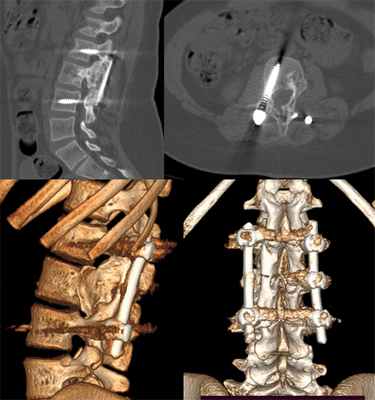

Если образование имеет крупные размеры, дополнительно требуется установка фиксирующих систем. Они стабилизируют прооперированный позвоночно-двигательный сегмент, исключают риск смещения и дополнительно укрепляют позвонок.

Вопрос об удалении АКК, расположенных в шейном отделе позвоночника, стоит несколько особняком из-за своей сложности. Хирургический метод считается радикальным методом лечения, однако частота рецидивов данной локализации составляет до 30 % [13, 14]. Зачастую выполняется ламинэктомия, изменяющая анатомо-биомеханические характеристики связочного аппарата в данной области и, соответственно, увеличивающая риск возникновения постламинэктомического кифоза [7, 15–17]. Тактика стабилизации позвоночника у детей (возрастом менее 10 лет) остается дискуссионной, учитывая высокую частоту осложнений и потенциал проста позвоночника. В таких случаях часто предпочитают сочетание фиксации с ортезированием, как с целью послеоперационной иммобилизации , так и с целью дополнительной коррекции. [18–20].

Транспедикулярная фиксация рассматривается многими авторами как необходимый компонент лечения, позволяющий предотвратить формирование постламинэктомического кифоза и возникновение повреждений невральных структур [18, 21–24]. Существует мнение [16], что металлофиксация нужна при резекции более чем 1 суставногоотростка. В настоящее время популярна точка зрения, что для фиксации позвоночника металлоконструкцией, должна присутствовать нестабильность или ее угроза в отдалённый период [15, 16, 25, 26]. Данных по вопросам применения костно-пластического материала в сочетании с металлоконструкцией при аневризмальных костных кистах позвоночника при анализе литературы не выявлено.